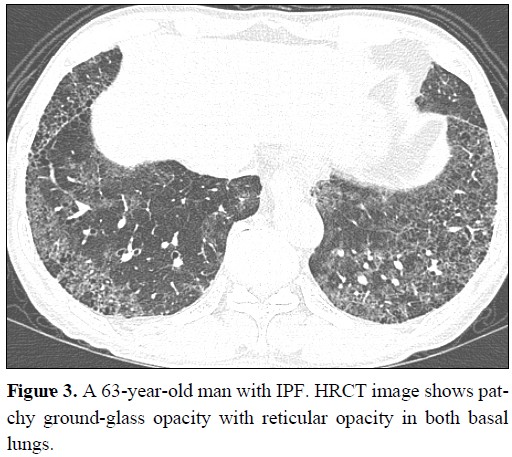

기질화 폐렴은 섬유 모세포 혹은 근섬유 세포를 포함한 육아조직이 폐포(허파꽈리)와 세기관지 내에 증식하는 폐질환을 말합니다. 기질화 폐렴은 원인에 따라 특발성 기질화 폐렴과 이차성 기질화 폐렴으로 나눌 수 있습니다. 특발성 기질화 폐렴은 원인이 밝혀지지 않은 것이고, 이차성 기질화 폐렴은 다른 질환에 의해 발생한 기질화 폐렴입니다. 남녀가 모두 같은 비율로 발생하고, 평균 연령은 50~60세에서 흔하며, 흡연과는 무관하게 발병합니다. 1. 기질화 폐렴 원인 특발성 기질화 폐렴의 원인은 아직 밝혀지지 않았지만 면역체계의 이상이 관련되어 있을 것으로 추측됩니다. 이차성 기질화 폐렴의 원인으로는 다음과 같은 것들이 있습니다. - 자가면역질환 : 루푸스, 류마티스관절염, 쇼그렌증후군 등 - 감염성 질환 : 결핵..